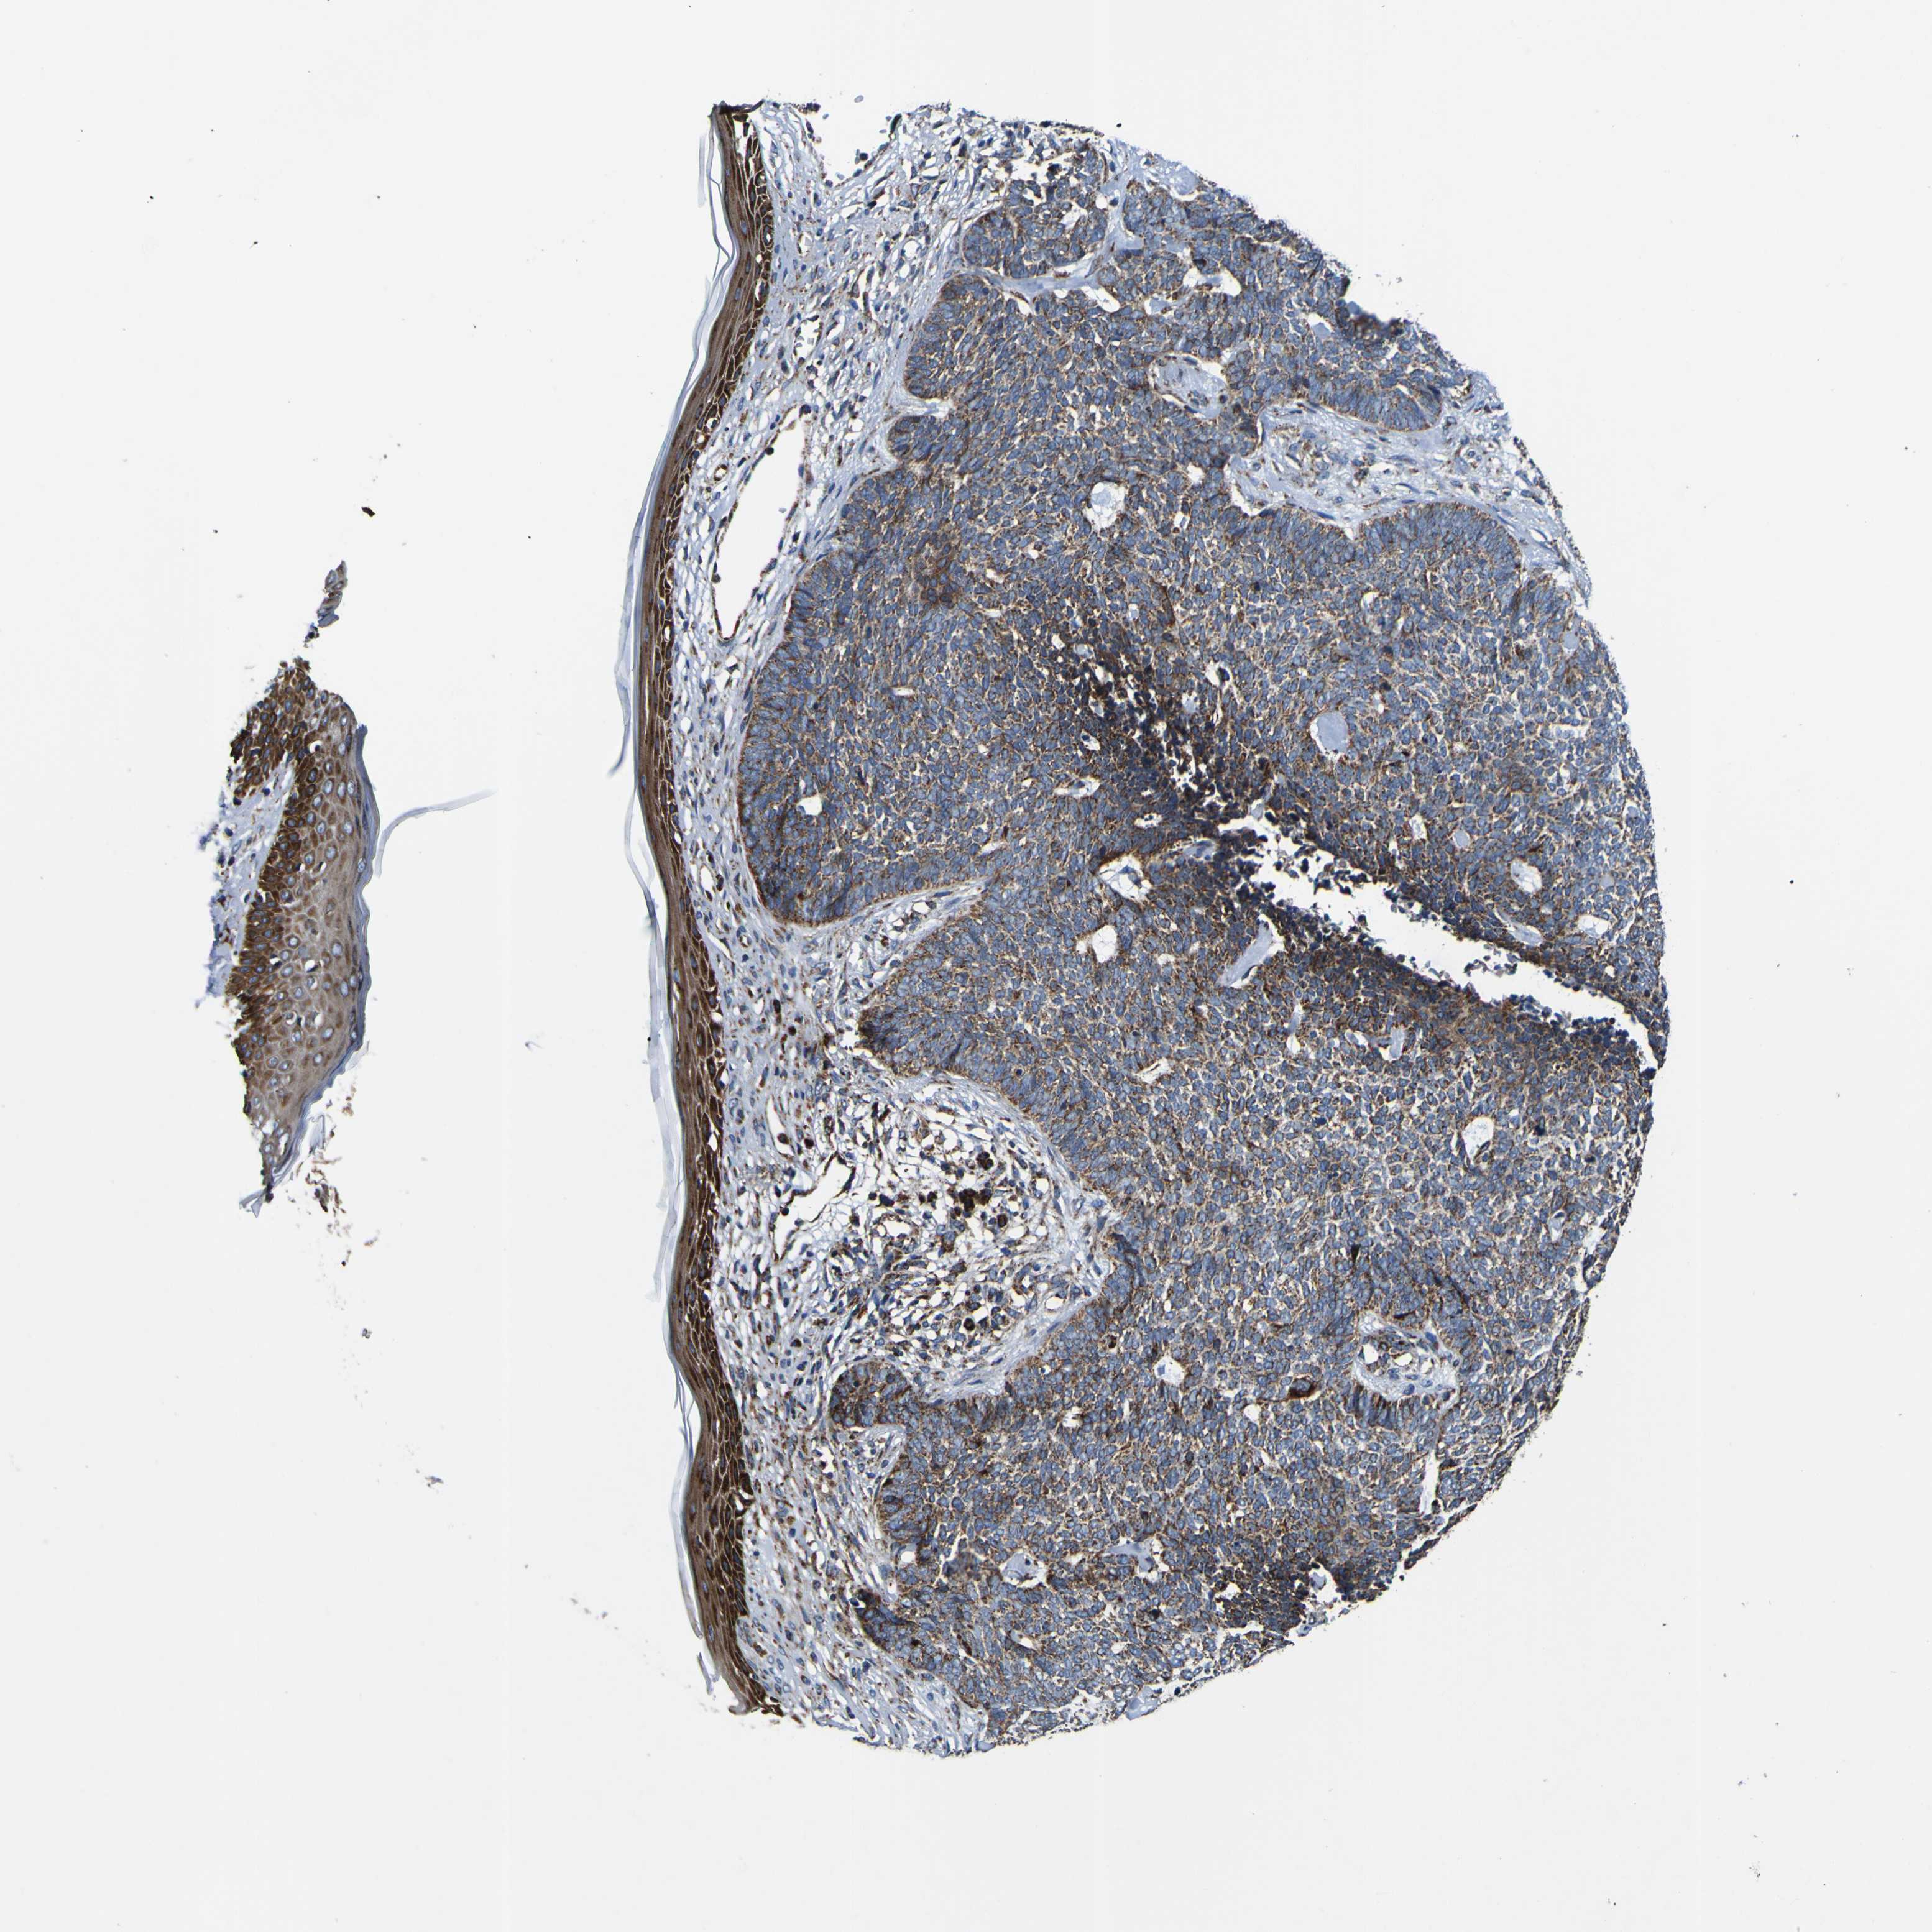

SKIN CANCER - Protein expressioni

A mouse-over function shows sample information and annotation data. Click on an image to view it in a full screen mode. Samples can be filtered based on level of antibody staining by selecting one or several of the following categories: high, medium, low and not detected. The assay and annotation is described here.

Each image is clickable and will lead to virtual microscopy that enables deeper exploration of all samples and also displays staining intensity scores, fraction scores and subcellular localization as well as patient and tissue information for each sample.

Antibody HPA012897

Squamous cell carcinoma, NOS